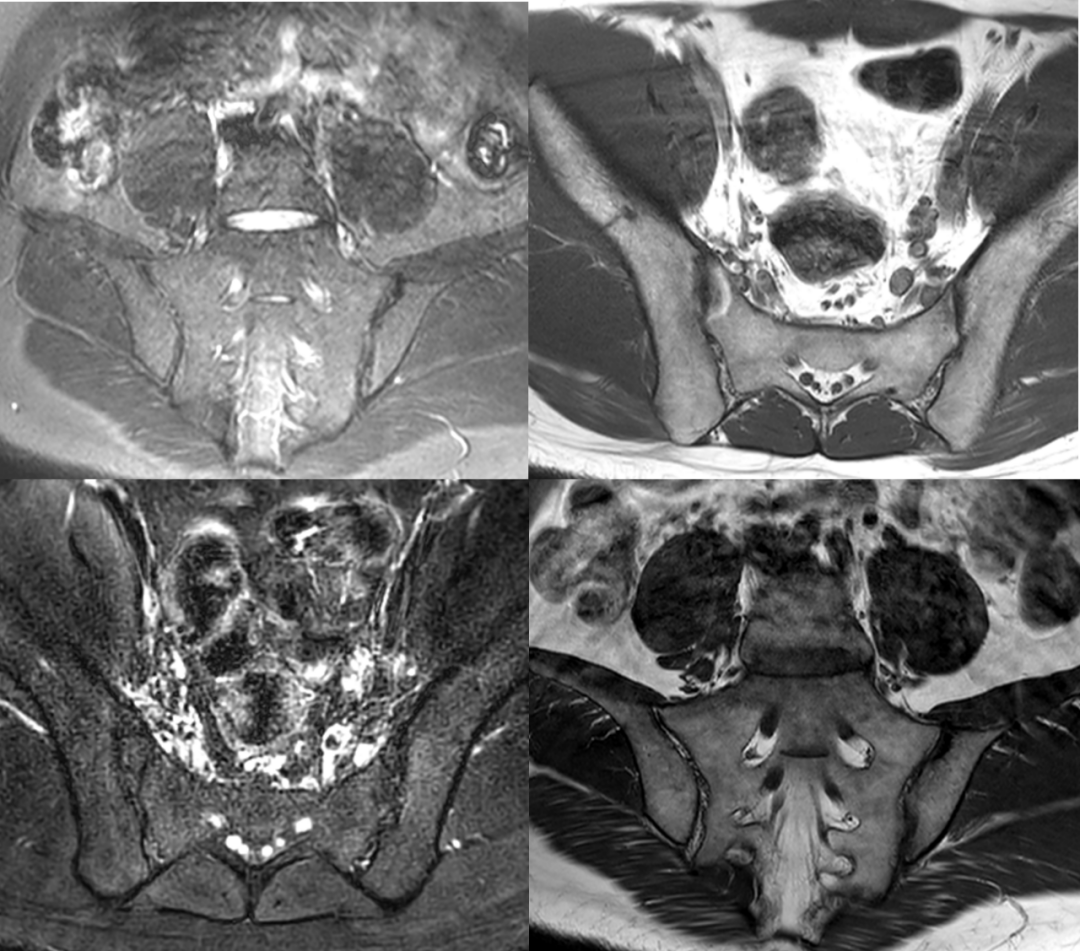

- 影像学检查,如X光或核磁共振成像